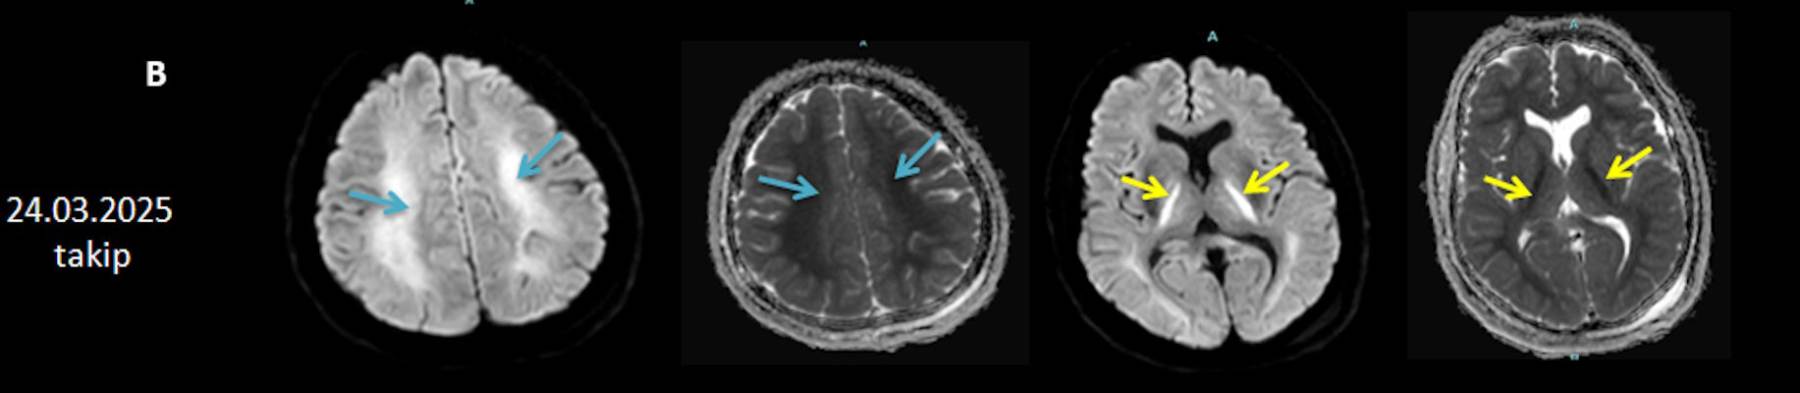

- B) 9 gün sonraki difüzyon MR incelemede kortikal ve bazal ganglionlardaki difüzyon kısıtlamalarının gerilediği, bilateral serebral beyaz cevherde (oklar) ve internal kapsül arka bacağı- kortikospinal trakt boyunca (oklar) yaygın DAG hiperintens, ADC hipointens difüzyon kısıtlamalarının geliştiği izleniyor.